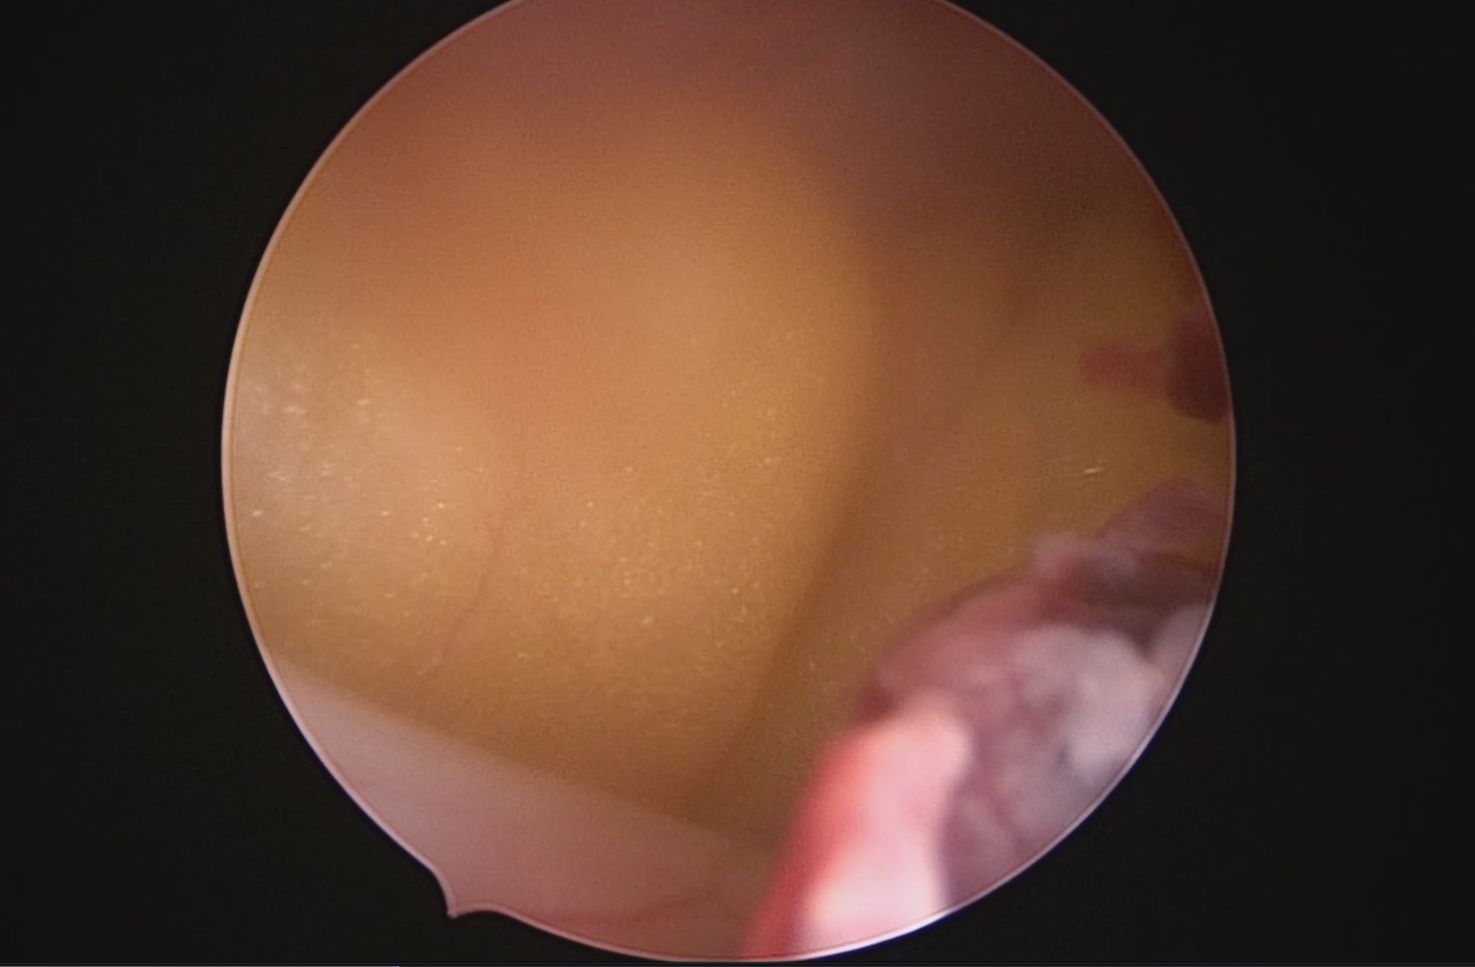

患者54岁,G2P1,顺产1次。安环26年,绝经1年,外院取环失败,子宫穿孔。宫腔镜术前B超提示子宫前位,盆腔未见异常。子宫极度前倾前屈位,宫腔下段后壁偏右穿孔,宫腔镜进入盆腔,见肠脂垂,未见积血,宫腔镜退出盆腔,寻找节育环。手术大部分时间在寻找宫颈内口和宫腔方向,在子宫穿孔的左上方找到宫颈内口,宫腔镜艰难进入宫腔,异物钳取环就迎刃而解了,取出一枚O型环。